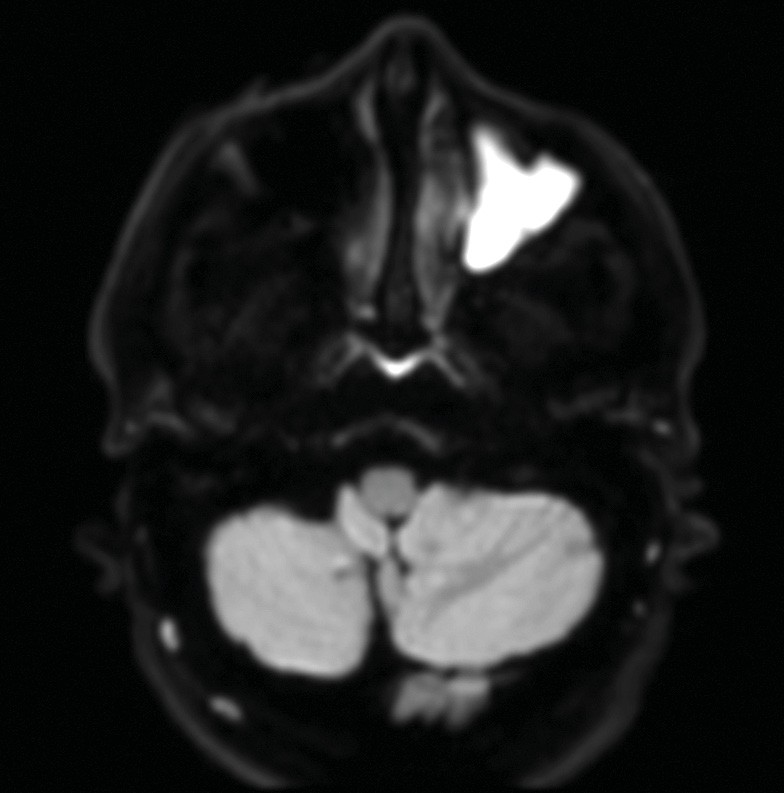

La tomodensitométrie des sinus retrouve un comblement complet unilatéral du sinus maxillaire gauche et des cellules ethmoïdales antérieures homolatérales, sans image de densité calcique intrasinusienne et sans lyse osseuse des parois (fig. 1). L’IRM montre un épaississement tissulaire de 23 mm de grand axe en regard du méat moyen gauche, avec un aspect de signal T2 hétérogène (fig. 2) et prenant le contraste en masse (fig. 3). Le comblement maxillaire gauche associé à un épaississement muqueux en cadre rehaussé correspond à une rétention en hypersignal en diffusion (fig. 4), avec diminution du coefficient apparent de diffusion (moyenne à 433 mm2/s) en faveur d’une pyocèle (fig. 5).